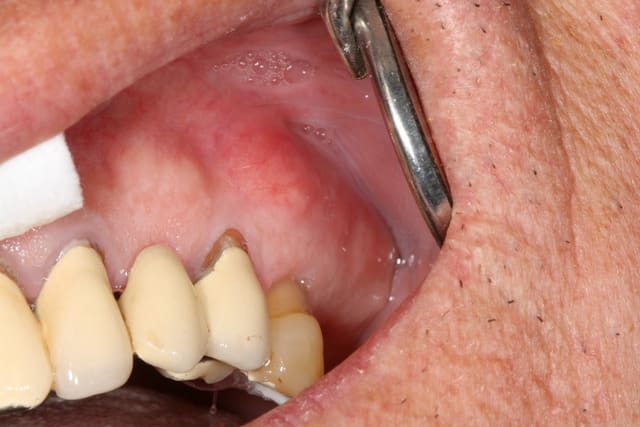

patiente de 80ans, canine incluse depuis donc pas mal de temps. ATCD de prothese amovible depuis 15ans. Je crains que sa canine soir hyper ankylosé et je me propose donc d'implanter au travers.

je n'ai jamais pensé que c'était la meilleur des solutions; néanmoins, si la canine est ankylosée (au bout de 65ans planquée dans l'os y'a des chances),son extraction va pas être sympa, risque de compromettre le bridge antérieur et donc de finir en all on 6 (dont le coût tissulaire, et financier et temps de traitement n'est pas le même).

extraire une canine de ce type pour une pose d'implant provoquera bien plus de dégâts que si tu implante dedans .

C'est bien ma crainte mais j'ai plusieurs questions : les forets antogyr ne risquent-ils pas de déraper au contact de la racine de 13 ?